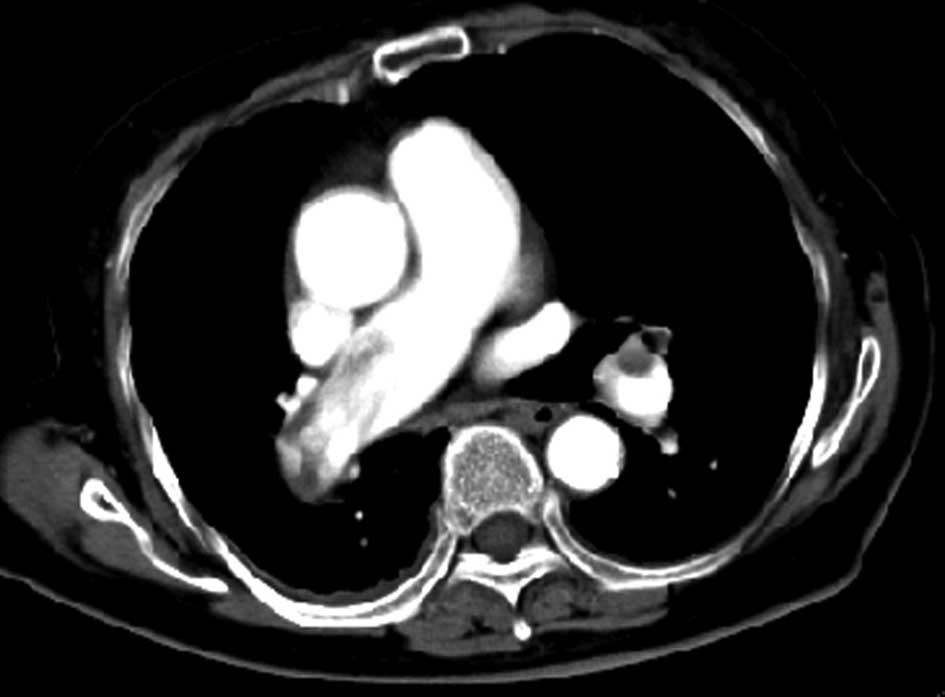

After admission, ‘reflex syncope’ was suspected and the patient was administered oral calcium antagonists (Nimotop 30 mg qd) and intravenous Alprostadil for injection (Alprostadil 10 μg qd) to boost the cerebral circulation, without effect. A further episode of syncope occurred during the 18 h after admission and the patient was transferred to the Department of Respiratory Medicine for a D-dimer assay, which indicated a value of 1,200 μg/l. An enhanced chest computed tomography (CT) scan revealed filling defects in the right main pulmonary and left inferior pulmonary arteries, as well as bilateral pleural effusion (Fig. 1). Color ultrasonography of the heart revealed a dilated right ventricle and right heart overload, severe tricuspid regurgitation and severe pulmonary hypertension and the systolic pulmonary arterial pressure was 130 mmHg (Fig. 2). The patient was finally diagnosed with MPE.

Figure 1

Enhanced chest computed tomography (CT) scan revealing filling defects in the right main pulmonary artery and left lower pulmonary artery branch, as well as bilateral pleural effusion.